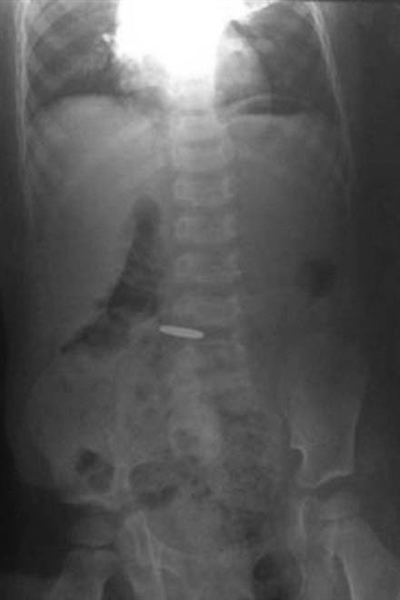

X光片显示:一幼儿的消化道内,有一个一元硬币大小物体(圈内)。图片来自微博

该微博还发布了孩子的X光片。光片显示:一幼儿的消化道内,有一个一元硬币大小物体。